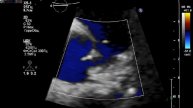

Конкурс Мы за ЗОЖ - МБОУГСОШ УЗИ сердца пролапс который не пролапс.

УЗИ сердца пролапс который не пролапс. Цена подарок.

Версия на АФ Визуализация стента в левой коронарной артерии.

Визуализация стента в левой коронарной артерии.